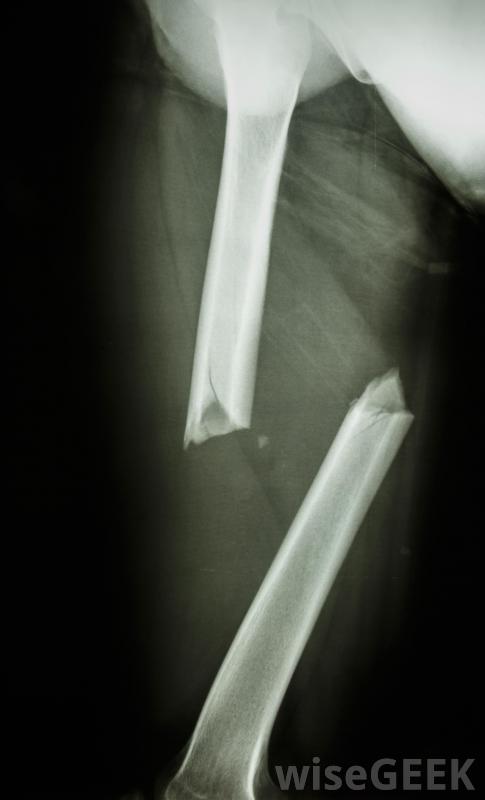

撞擊性骨折,當一塊骨頭碎裂,碎片被打入其他骨塊,可能是相當嚴重的,一旦確定損傷程度,應迅速治療,以避免進一步的問題。如果損傷不太嚴重,石膏、夾板或吊索可能足以將受傷的骨頭固定在適當的位置,以便愈合是的。更廣泛的骨折和多個骨碎片可能需要手術將它們放回原位,并且可能需要螺釘或銷釘之類的硬件來固定它們。由于這些類型的骨折通常非常痛苦,因此在愈合過程中可能需要藥物來控制它嚴重的撞擊骨折通常需要使用鋼板、桿和螺釘來重新對齊骨骼損傷不太嚴重,固定可能足以治療。醫生通常會用X光片、核磁共振成像或CT掃描來檢查骨折的嚴重程度和碎片的位置。較輕的骨折可以用夾板、吊索固定,或石膏,使受影響的區域保持不動。這樣可以防止骨頭的末端互相摩擦或進一步相互推進,并使骨頭愈合。可能有必要在相當長的時間內盡量減少受傷區域的移動,即使在取出石膏或夾板之后,因為撞擊骨折通常愈合得很慢阻生性骨折在完全愈合之前會嚴重限制活動性,尤其是在老年人中。當阻生骨折涉及大量骨碎片時,手術可能是必要的。嚴重粉碎的骨頭通常需要重建,以避免進一步的損傷和正確的愈合。外科植入物,如金屬螺釘、金屬棒或金屬針也可能需要使用,以保持骨頭的正確連接。術后,受影響區域可能需要在石膏或吊索上放置一段時間,以限制活動并使碎片重新團聚。X光片將顯示骨頭骨折的嚴重程度由于骨折的嚴重程度通常與阻生性骨折有關,這種情況通常會給患者帶來大量的疼痛。盡管疼痛程度因人而異,且隨著損傷程度的不同,但疼痛往往是痛苦的為了控制這種程度的疼痛,醫生可能會建議使用止痛藥。止痛藥的種類可能取決于病人的不適程度;非處方藥如非甾體抗炎藥對一些人來說可能足夠了,而其他人可能需要處方手術后,受影響區域可能需要一段時間的石膏或吊索,以使骨碎片重新結合。可以要求CT掃描來確定撞擊骨折的嚴重程度對于嵌頓骨折的治療可能需要手術。吃東西很重要骨折手術后要吃大量的水果和蔬菜。